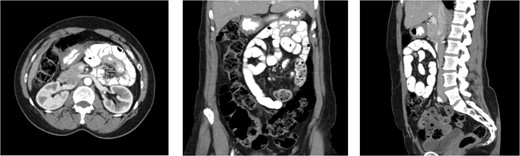

A 45-year-old morbidly obese male with a history significant for morbid obesity and atrial fibrillation presented with 1 day of abdominal distension, oral intake intolerance, nausea, and vomiting. The patient had no history of abdominal surgery. Physical exam revealed a soft, distended abdomen without peritoneal signs. Laboratory evaluation revealed normal blood cell counts and electrolytes. A CT-scan of the abdomen and pelvis with IV and PO contrast was performed which demonstrated proximal small bowel dilation and a significant amount of small bowel posterior to the SMA. A mesenteric swirl was also observed on CT imaging. The CT scan images are presented below (Fig. 4). Based on the concern for closed-loop obstruction and probable paraduodenal hernia, the patient was taken for diagnostic laparoscopy. During the procedure the patient was noted to have marked small bowel dilation, and most of the small bowel was found incarcerated behind the ascending mesocolon. The laparoscopic approach in this patient was significantly hindered by the excessive intraperitoneal fat present from his morbidly obese state. The procedure was converted to an upper midline laparotomy which facilitated complete reduction of the hernia and evaluation of the incarcerated bowel. Post-reduction, the bowel was deemed well perfused and viable. The internal hernia defect was confirmed as Waldeyer’s fossa based upon its position between the SMA and the ligament of Treitz. The hernia sac was opened laterally by mobilizing the cecum and ascending colon, taking down the white line of Toldt and medializing the ascending colon and cecum. Appendectomy was performed. The operation was completed without complication and the patient recovered well.

CT images for Case 2, axial, coronal, and sagittal, respectively. Note the mesenteric swirl (arrows in axial and coronal images) around the SMA (single arrowhead in axial and coronal images). This represents the posterior torsion of the small bowel mesentery as it courses into Waldeyer’s fossa toward the right retroperitoneum. The resulting dilated small bowel can be seen in the right upper quadrant. Also note the anterior course of the proximal transverse colon (three arrowheads in the sagittal cross-section) as it has been pushed toward the anterior abdomen due to the significant mass of dilated small bowel which is now posterior to its mesentery.